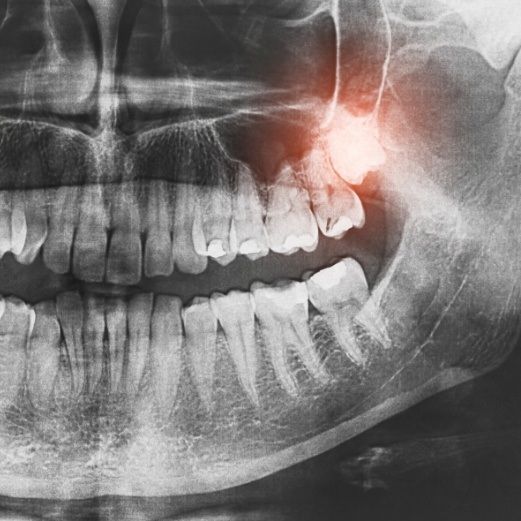

Wisdom Tooth Extractions

Wisdom teeth, also called the third molars, typically grow in between the ages of 16 and 21. If you’re at-risk of developing infections, experiencing pain, or don’t have enough room for them to grow into your mouth without causing your other teeth to become misaligned, we offer surgical and simple wisdom tooth extractions. Learn whether your third molars need to be removed by scheduling a consultation with our team!